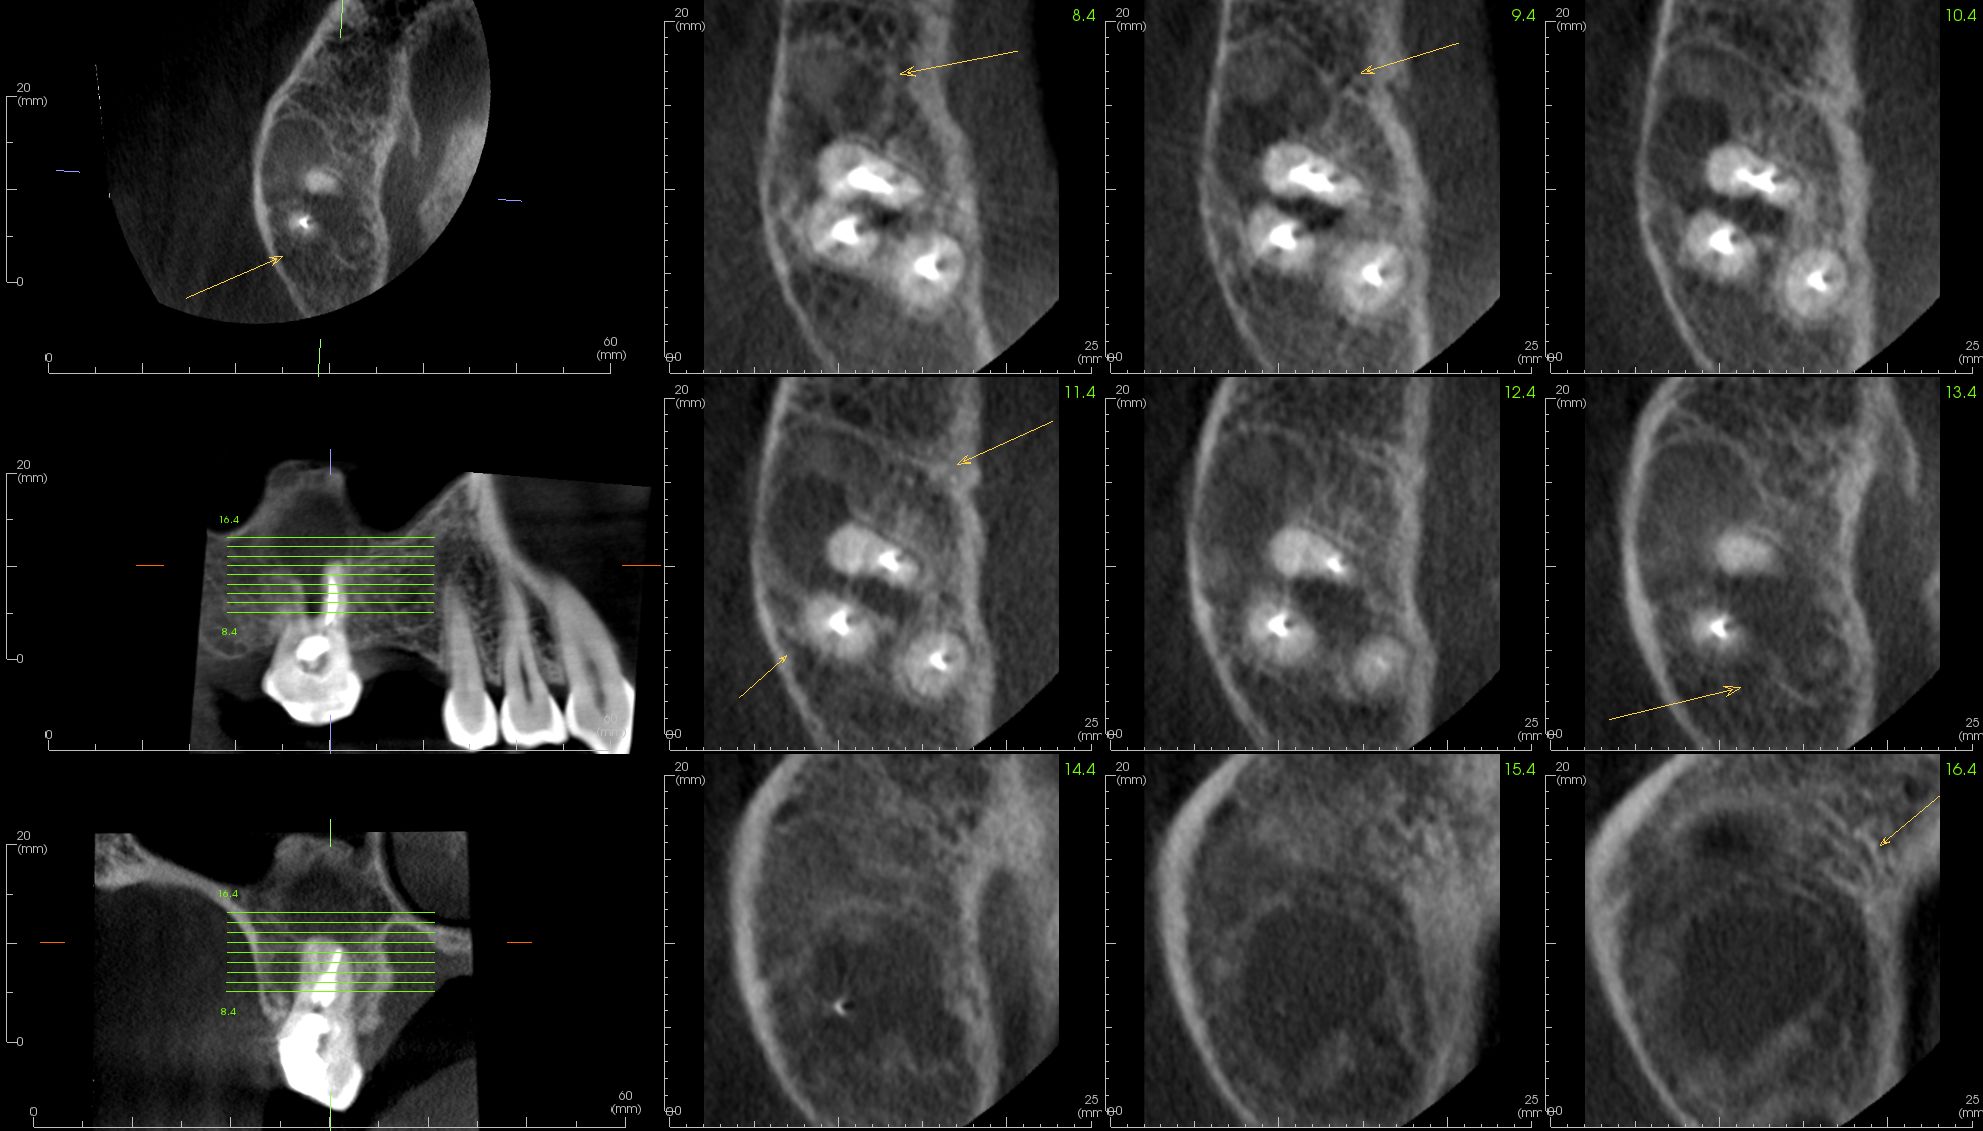

Image Portfolios visually communicate the imaging goals to you and your patient.